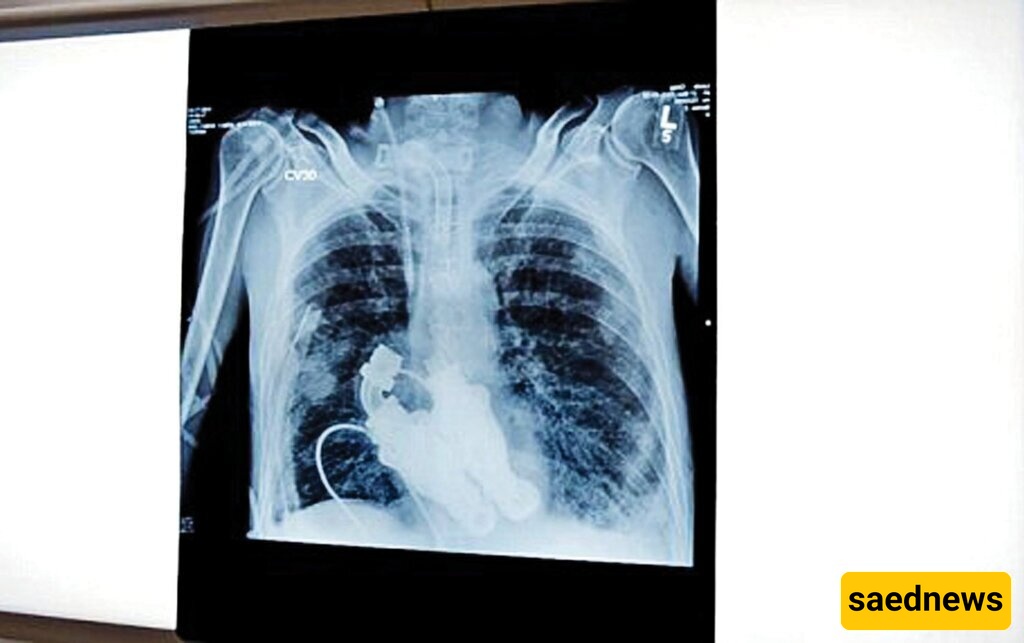

The device placed in Craig’s chest functions like a turbine, propelling blood through his body. It uses broad, blade-like components to circulate blood without any pumping action. While other patients, including former U.S. Vice President Dick Cheney, have similar devices, those typically assist one of the heart’s ventricles rather than completely replace the heart.

In the operating room, Craig’s family anxiously awaited news. When the doctors emerged, they confirmed the procedure was successful—but the true test was whether Craig would regain consciousness. Astonishingly, he did. He opened his eyes and even spoke with the attending physicians.

Craig remained in the intensive care unit. Doctors and nurses placed stethoscopes on his chest, but no heartbeat was heard—only a faint whirring sound. His wife, Linda, recalls the moment vividly: “I listened closely, and all I could hear was a buzzing. It was unbelievable. He had no heartbeat—because he had no heart.”